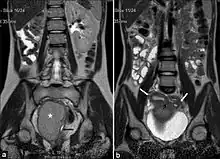

(a) Coronal Single shot T2W image shows absence of the right kidney. The distended hemivagina (asterisk) is seen on the right side and the normal collapsed left hemivagina with minimal fluid is seen adjacent to it (black arrow). The distended hemivagina ends above the introitus and its contents are hypointense to fat. (b) Coronal Single shot T2W image shows right and left uterine horns (white arrows). The right uterine horn cavity is seen to communicate with the upper end of the fluid collection in right hemivagina (small black arrow)